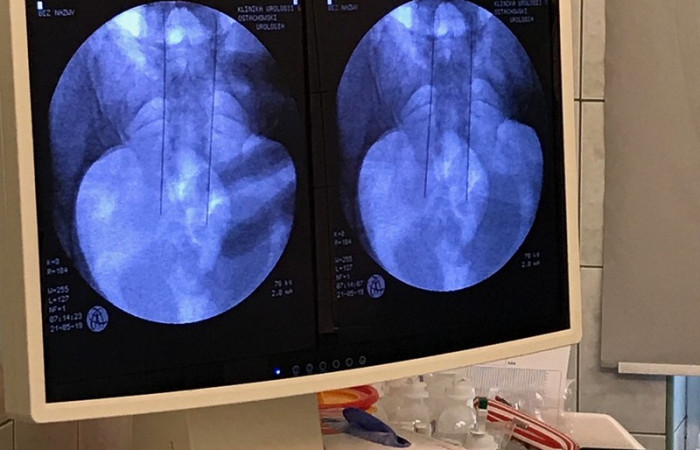

Lekarze O/K Urologii i Urologii Onkologicznej Szpitala Uniwersyteckiego w Krakowie pod kierownictwem prof. dr hab. med. Piotra Chłosty, przeprowadzili z udanym skutkiem pierwszy refundowany przez NFZ zabieg neuromodulacji krzyżowej. Polega on na wszczepieniu specjalnej elektrody, która stymuluje prawidłowe działanie nerwów i pęcherza moczowego. Pacjentka, u której przeprowadzono zabieg czuje się dobrze i już dostrzega znaczną poprawę komfortu życia.

Jak zapewniają lekarze, zabieg neuromodulacji krzyżowej jest to minimalnie inwazyjna, bezpieczna i skuteczna metoda leczenia schorzeń dolnych dróg moczowych: nietrzymania lub zatrzymania moczu. Polega na wszczepieniu elektrody wraz z symulatorem w obrębie korzeni nerwowych. Stymulowane w ten sposób nerwy wysyłają sygnał do pęcherza moczowego i pobudzają go do prawidłowego działania. Dzięki temu pacjenci – w zależności od schorzenia – mogą regulować ilość i częstotliwość oddawania moczu. Samo urządzenie nie jest natomiast większe niż…pilot do samochodu.

Kluczem do skuteczności tej terapii jest prawidłowa kwalifikacja pacjentów – wyjaśnia dr med. Mikołaj Przydacz, który przeprowadzał zabieg. - Nie każdy pacjent mający problemy z funkcjonowaniem pęcherza moczowego nadaje się do przeprowadzenia takiego zabiegu. Ważne jest, by ta metoda przyniosła wyraźną poprawę, dlatego choć elektroda wszczepiana jest na stałe, pacjent przez kilka tygodni testuje ją korzystając z zewnętrznego „pilota” z kilkoma różnymi programami. Dopiero po tym czasie - podczas kolejnego zabiegu – najczęściej pod skórę na pośladku - implantowany jest stały generator impulsów – tłumaczy.